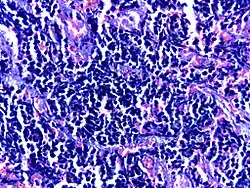

Small cell carcinoma of lung | Micograph of small Cell Carcinoma Lung. The tumor appears blue because the malignant epithelial cells are small with scanty cytoplasm, nuclei shows finely granulated chromatin. Cells are seen in clusters. There is nuclear overlapping with moulding and crushing. | Category: Histopathology of small cell lung cancer | Small cell lung cancer |

![]() |